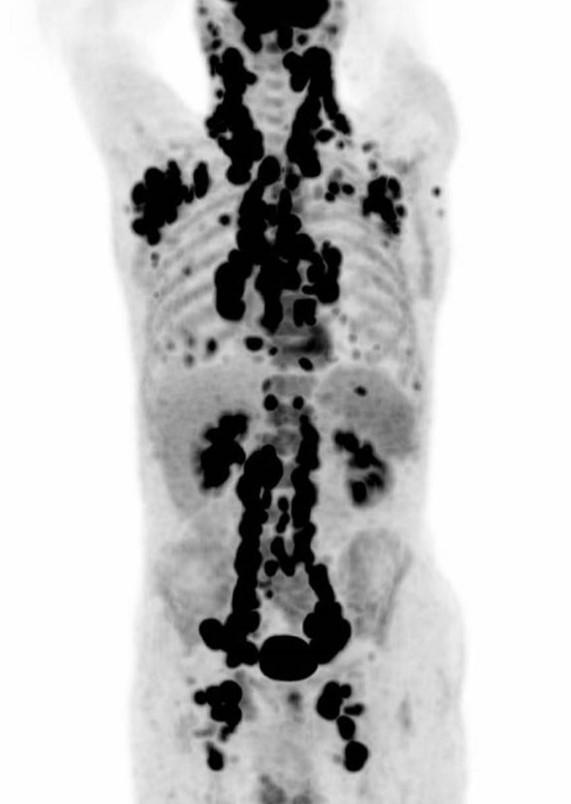

*69 years old male patient.

Answer: Non Hodgkin Lymphoma

69 years old male patient with Non Hodgkin Lymphoma. PET-CT showed lymph node enlargement with high FDG uptake on all lymph node stations.